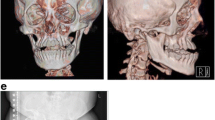

The boy harboring the CREB3L1 variant (patient no. 6) had no family history of OI or tooth agenesis. None of the four siblings were affected by OI or tooth agenesis. At the time of the oral examination, the proband presented with a mixed dentition. Investigation revealed six missing permanent tooth germs, all premolars, and a severe malocclusion including mandibular overjet, unilateral open bite, and bimaxillary crowding (Fig. 2). The boy exhibited neither clinical nor radiographic signs of DGI in the deciduous or permanent dentitions (Table 1). Further details regarding the non-dental findings in the proband have recently been described in detail [40].

Clinical and radiographic findings in a 12-year-old boy identified with a CREB3L1 variant. (a) A severe malocclusion with crowding and lateral open bite on the right side and cross-bite on the left. No clinical signs of dentinogenesis imperfecta (DGI). (b) Panoramic radiograph showing absence of six permanent tooth germs in the premolar regions. The radiograph is difficult to interpret due the extensive crowding. No signs of DGI

To our knowledge, this is the first time the dental and maxillofacial phenotype of an individual with a CREB3L1 variant has been described in detail. Our patient presented with oligodontia and severe malocclusion including a mandibular overjet, unilateral open bite, and bimaxillary crowding. However, no DGI could be detected clinically or radiographically. We previously reported that presence of clinical and radiographic signs of DGI is associated with mutations in COL1A1 and COL1A2 that cause a qualitatively changed protein [41]. Based on our findings, we suggest that homozygous loss-of-function mutations of CREB3L1 may contribute to arrest of tooth development in specific dental developmental areas but is not enough to cause severe signs of DGI. The expression of collagen type I is seen early in tooth development. In the rat, expression has been detected in the dental epithelium and mesenchyme during the bud stage and during the cap and bell stages [43]. The secretion of predentin is initiated during the late bell stage of tooth development. This may indicate that cells are more sensitive to CREB3L1 during earlier stages of tooth development, where the altered secretion of collagen type I and its interaction with modifier genes may contribute to arrest of tooth development and cause dental agenesis. Lindahl et al. found markedly low levels of CREB3L1 mRNA in primary human osteoblast-like cell (hOB) (16%) and fibroblasts (21%), but collagen I levels were only reduced I hOBs (5–10%) indicating tissue-specific sensitivity [40]. OI-causing loss-of-function mutations in CREB3L1 have been described in two consanguineous families in two previous studies [7, 44]. These studies reported a 3-bp in-frame deletion (p.Lys312del, c.934_936delAAG) in exon 7 [44] and a homozygous whole gene deletion [7]. In the study by Keller et al. [44], heterozygous carriers of the variants were mildly affected by OI and homozygosity caused prenatal/perinatal lethal OI similar to that seen in OI type II. Except for reduced skull mineralization, no other craniofacial characteristics of probands presenting with homozygous variants in CREB3L1 have been described. However, a heterozygous carrier was found to have blue sclerae, but normal teeth [7]. Since complete loss of CREB3L1 causes prenatal/perinatal lethality as in both of the previous cases, we believe that, since the nonsense mutation is relatively close to the 3′ end of CREB3L1, the transcript might escape from nonsense-mediated decay and translate into a partially functioning protein with a missing C-terminal end.